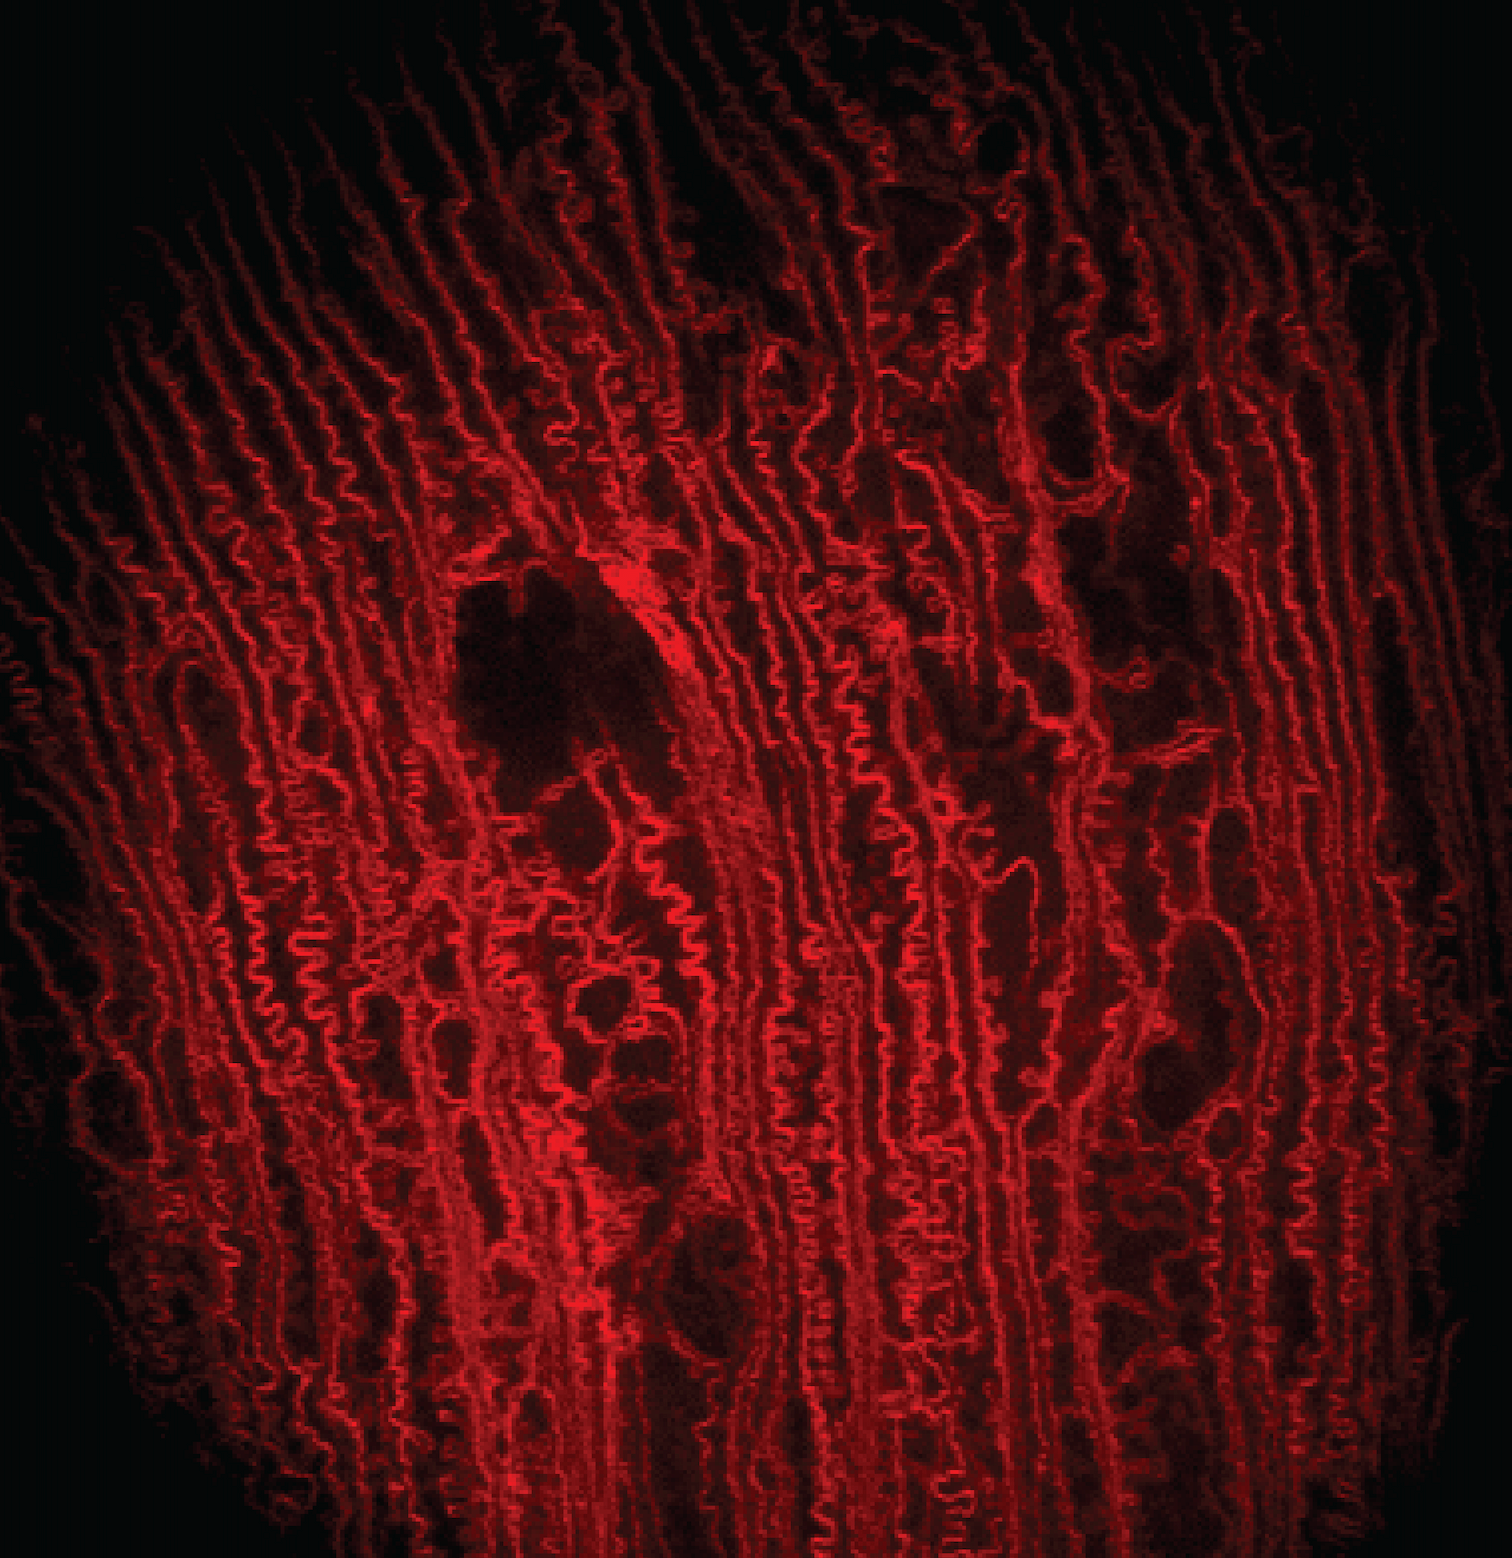

My postdoctoral training at the University of California, Berkeley was focused on the development of two photon fluorescence microscopy (TPFM) and adaptive optics for in vivo imaging of ocular lenses in genetic mouse models. Traditionally, microscopic studies of the cellular organization of mammalian lenses have been carried out ex vivo on dissected lenses, which eliminates both in vivo environment for supporting lens internal circulation and attached zonules for regulating lens accommodation. Our work has demonstrated that two photon fluorescence microscopy and adaptive optics can enable in vivo visualization of lens cells in transgenic mice that express fluorescent proteins in lens cell membranes. We employed direct wavefront sensing to measure and correct aberrations to image cellular organization deep inside the anterior part of the lens and discovered novel features in different regions up to near the lens core that have not been observed in prior ex vivo studies. These studies demonstrated the importance of in vivo imaging in preserving the native biological context in live animals and opened a new route for observing changes in lens cell morphology during normal development and pathological processes.

Paidi SK et al., Investigative Ophthalmology and Visual Science (iOVS), 2023